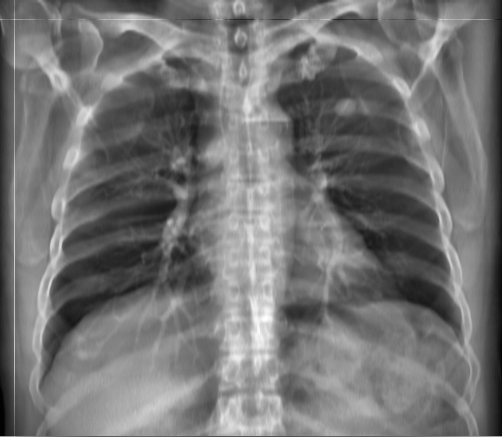

3.3 Applicability to Real X-ray

In order to explore the applicability of our algorithm to real X-ray and to examine whether the enhancement scheme introduces artifacts detrimental to CAD detection performance, we chose to perform the lung enhancement algorithm as a preprocessing step on nodule and mass CAD input images.

To accomplish this, we trained and tested a CheXNet [5] based network on 67,313 images released in ChestX-ray14 dataset(subset of PA images). In Figure 8 we show the results of the enhancement on an image from NIH ChestX-ray14 dataset [4]. The architecture we chose was a DenseNet-121 based network, with 512×512512512512\times 512 input size. Network weights were initialized with pretrained ImageNet weights and training was performed independently for enhanced images and non-enhanced images.

The dataset was split to 44,971 training, 11,245 validation and 11,097 test images. Results are given on the official test set in terms of average precision (AP) for the labels mass and nodule. We see a moderate increase in AP scores for the mass detection task (Table 2).

Refer to caption

(a)

(b)

(c)

(d)

Figure 8: Enhancement result on NIH ChestX-Ray14 image. One network was trained on the original X-ray and a second network was trained on the enhanced X-ray (a) Original X-ray (b) Enhanced X-ray (c) Zoom (d) Zoom -Enhanced